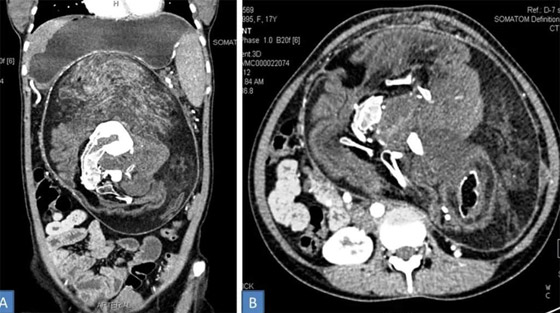

4- جنين داخل جنين:

أحيانًا يستطيع توأم مغاير خارجي التواجد بشكل كامل داخل توأمه الذي يكون سليمًا، وهو ما يعرف باسم "الجنين داخل الجنين" أو Fetus in Fetu. هي ظاهرة نادرة للغاية، حيث لم يتم توثيق أكثر من 200 حالة عبر التاريخ، وعادة ما يكون هنالك جنين واحد داخل الجنين، لكن في إحدى الحالات وجد الأطباء 11 جنينًا داخل جنين.

إنها ظاهرة طاف حولها جدل كبير بين الباحثين والعلماء حول الطريقة التي تحدث بها، كما أن بعضهم لا يتفق حتى على أن "الجنين" الداخلي يعتبر توأمًا أساسًا، حيث يعتقد هؤلاء أن ظاهرة "الجنين داخل الجنين" ما هي إلا حالة ورم مسخي متطور، الذي هو عبارة عن ورم يتكون من عدة أنواع من أنسجة الجسم.

كما يوجد فريق آخر من الباحثين الذين يعتقدون بأن الظاهرة تحدث بسبب وقوع خلل أثناء تطور الجنين، حيث تنقسم بعض الخلايا الجذعية التي من المفترض أن تتطور لتصبح أعضاءً أخرى بشكل غريب. لكن آخرين يقولون بأنه توأم حقيقي، ذلك أن الجنين داخل الجنين يملك عمودا فقريًا، وغالبا ما تتطور لديه أعضاء مثل أطراف الجسم.

بالطبع قد يكون أي من الآراء والنظريات السابقة صحيحًا، حيث قد تكون هنالك الكثير من الطرائق المختلفة التي تنتهي بجنين متطور بشكل جزئي داخل جنين آخر متطور بشكل كامل. قد يعني هذا أن دراسة هذا النوع من التوائم قد يساعد الأطباء على فهم كيف أن بعض الأورام الجنينية تصبح مصدر إشكال بينما تبقى أورام أخرى حميدة، كما قد تساعدنا على فهم بعض الأمور المثيرة حول البرمجة التطورية للخلايا.

قد يكون حدوث ظاهرة الجنين داخل جنين راجعًا لكون أحد الجنينين يحتوي الآخر في مرحلة ما من تطورهما، أي أن الظاهرة أقرب إلى فكرة الالتحام لكنها أكثر تطرفًا. وهو ما لا يعتبر بعيد المنال مثلما قد يبدو عليه، لأنه توجد حالات موثقة لأجنة توأم يمتص أحدها جزءا من الآخر أو يمتصه ويحتويه بشكل كامل.